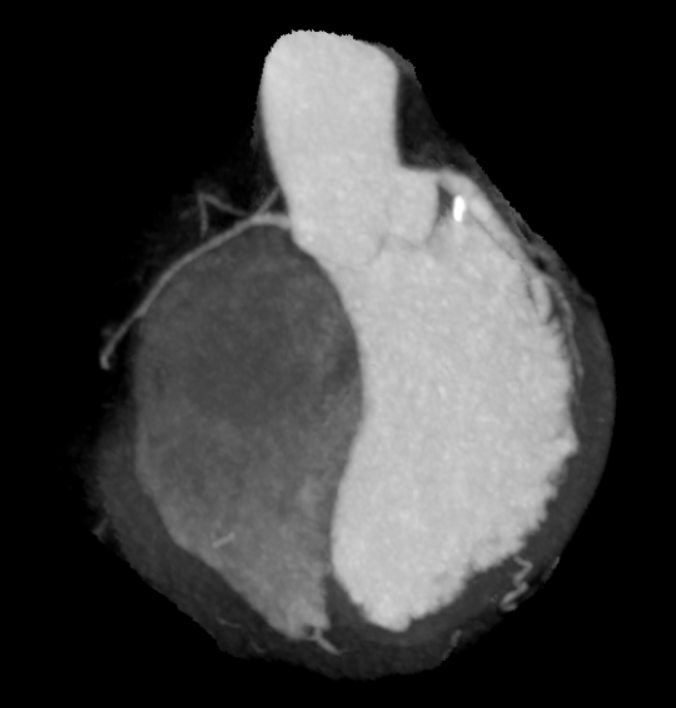

Διεξάγεται σε αξονικό τομογράφο πολλαπλών τομών (>128 detectors) με εξειδικευμένο λογισμικό απεικόνισης και επεξεργασίας των δεδομένων της παλλόμενης καρδιάς. Με την χρήση ακτίνων Χ, υπό ηλεκτροκαρδιογραφικό συντονισμό, διεξάγεται λήψη εγκάρσιων τομών της καρδιάς και με ειδική επεξεργασία δημιουργείται τρισδιάστατη εικόνα του καρδιακού μυ, των καρδιακών βαλβίδων και των στεφανιαίων αγγείων. Στον εξεταζόμενο χορηγείται σκιαγραφική ουσία που δίνει την δυνατότητα ανάδειξης στένωσης ή άλλων ανωμαλιών στις αρτηρίες.

Ακρογωνιαίος λίθος της διαγνωστικής αξίας της αξονικής στεφανιογραφίας είναι η δυνατότητα χαρακτηρισμού των αθηρωματικών πλακών (επασβεστωμένες, μικτής σύστασης, μη-επασβεστωμένες) ανάλογα με το ποσοστό εναπόθεσης ασβεστίου σε αυτές που καθοδηγεί την μετέπειτα κλινική απόφαση και θεραπεία.